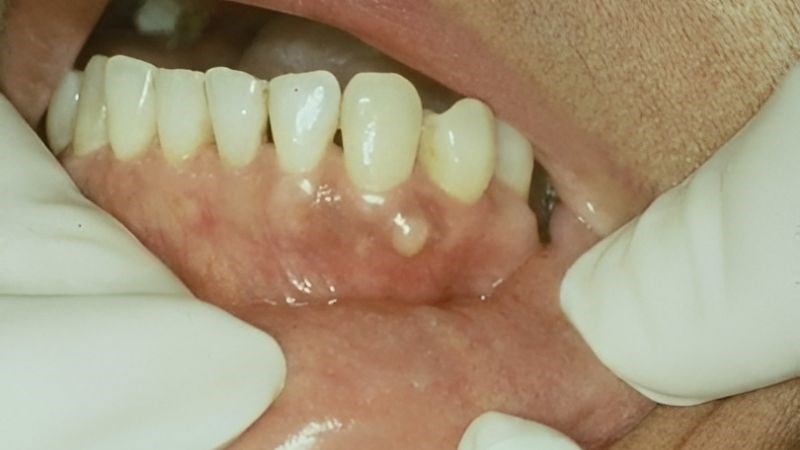

- Giai đoạn u hàm mặt phá vỡ bề mặt xương: Bờ xương xung quanh hàm mặt trở nên mỏng và sắc bén hơn. Bệnh nhân có thể sờ thấy khối u nhưng không gây đau.

- Giai đoạn u xương hàm tạo đường dò và gây biến chứng: Trong giai đoạn này, khối u sẽ tạo ra lỗ thủng ở mặt trong hoặc bên ngoài miệng, gây ra nhiều vấn đề và ảnh hưởng tiêu cực đến sức khỏe.